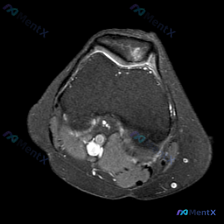

看到一份很有讨论价值的膝关节MRI读片病例,问题是判断影像中的异常,提示方向是半月板异常,整理一下完整分析思路跟大家分享。 病例影像基本信息 这是一张膝关节股骨髁间窝水平轴位T2加权MRI,可观察到的结构和征象如下: 1. 骨骼:股骨远端皮质完整,骨髓无明显异常水肿信号 2. 关节腔:可见明显的髌股...